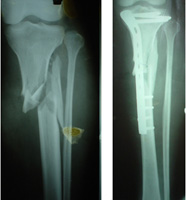

COMPLEX FRACTURES